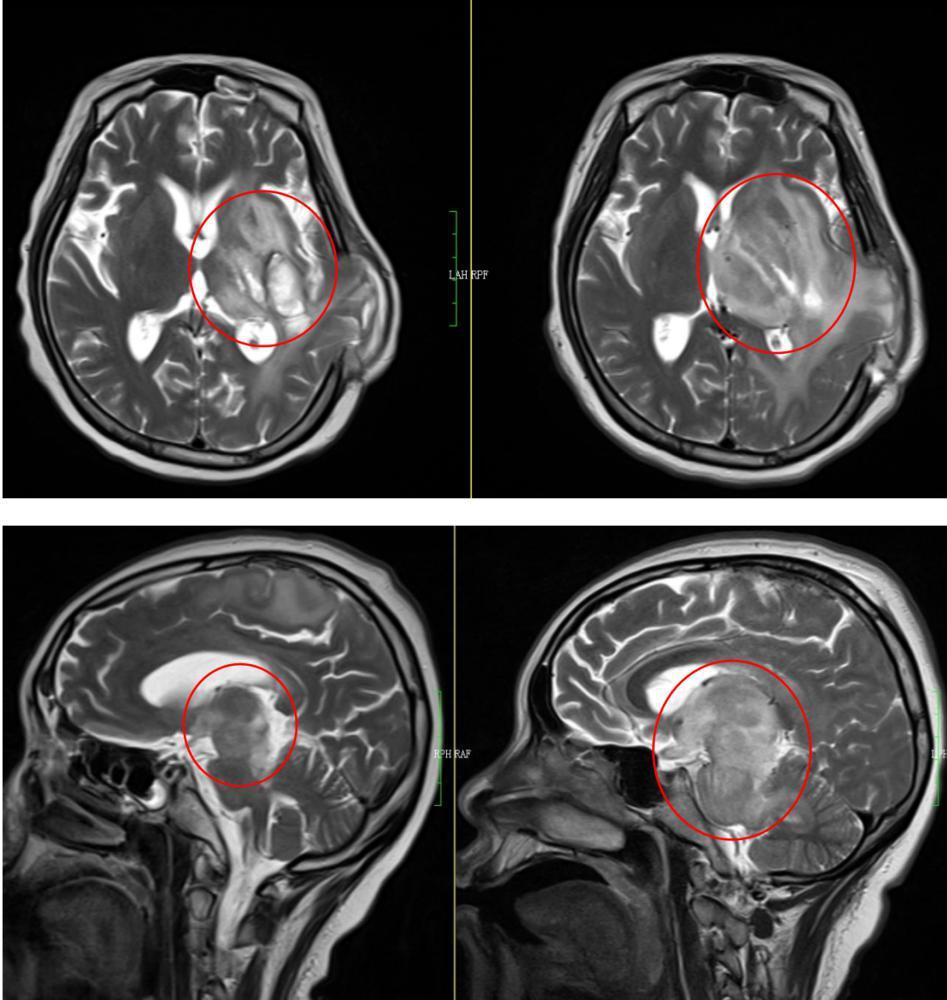

然而出于母爱的天性,小倩一直不同意处理脑部的肿瘤。但是这种合并妊娠期的肿瘤,往往进展很快。果然,情况很快就不容乐观。3月21日,小倩在全麻下进行了左侧额顶叶占位切除术+去骨瓣减压术。术后病理提示,小倩脑部的肿瘤为高级别胶质瘤,是世界卫生组织神经系统肿瘤分类中的4级胶质瘤,为恶性程度最高的一类肿瘤。4月1日,为了更好地处理小倩的问题,医生无奈地进行了“引产术”。此后又经过多家医院神经学专家持续不断地积极治疗,小倩虽然保住了性命,但进入4月中下旬后开始变得嗜睡,直到4月底彻底进入深度昏迷状态。专家们一致认为情况非常棘手,苏醒的可能性渺茫。

在该阶段放疗计划执行期间,小倩曾一度出现高热、喉部吸出大量黄色黏稠痰的症状,由于长期卧床又曾有大量激素冲击治疗,肺部影像学也提示肺部重症感染。为了更好解决这个问题,经讨论决定后,将小倩的化疗强度减弱,逐步降低激素的使用强度,同时配合抗细菌及抗真菌治疗。功夫不负有心人,小倩肺部感染的情况好转。在科室持续近一个月的治疗后,第一期的15次放疗计划顺利完成,小倩的状态也由深昏迷转为嗜睡,肿瘤大小缩退明显。好转的情况让小倩的父母非常高兴,也更加积极配合治疗。为了更好地保护患者的脑组织,石兴源主任建议重新定位,缩野放疗,在二段放疗计划中,照射野面积大大减少,也大大降低对正常脑组织的剂量限制。